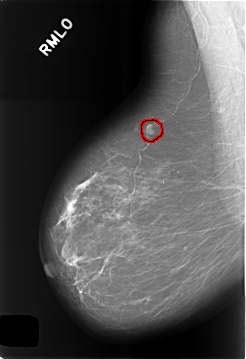

C_0485_1.RIGHT_MLO

RIGHT_MLO LINES 5736 PIXELS_PER_LINE 3928 BITS_PER_PIXEL 12 RESOLUTION 50 OVERLAY

FILE: C_0485_1.RIGHT_MLO.OVERLAY

TOTAL_ABNORMALITIES 1

ABNORMALITY 1

LESION_TYPE MASS SHAPE LOBULATED MARGINS CIRCUMSCRIBED

ASSESSMENT 3

SUBTLETY 5

PATHOLOGY BENIGN

TOTAL_OUTLINES 1

BOUNDARY